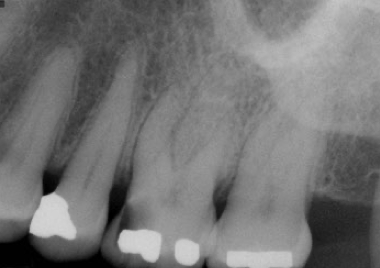

what radiographic analysis should be carried out during endodontic diagnosis?

A

• new periapicals (at least 2)

• bitewing

• cone beam-computed tomography